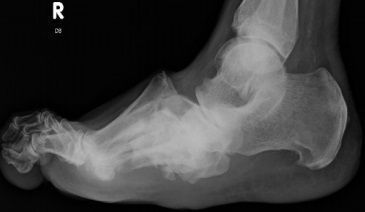

What disease is this? What does the arrow indicate? | Rheumatoid arthritis. Arrow = Bone erosion secondary to inflammation of retrocalcaneal bursa. |

What disease is this? What do the arrows indicate? | Gout Arrows = 'punched out' erosions |